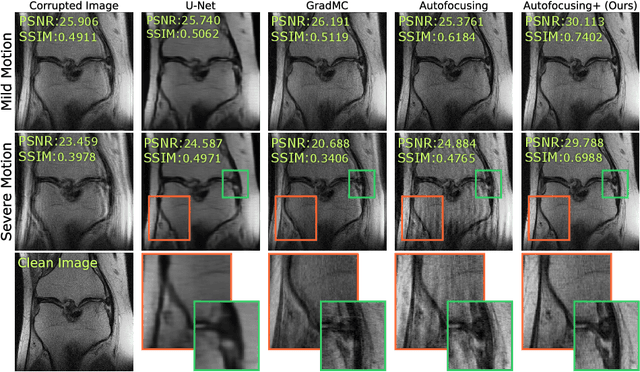

Abstract:Image corruption by motion artifacts is an ingrained problem in Magnetic Resonance Imaging (MRI). In this work, we propose a neural network-based regularization term to enhance Autofocusing, a classic optimization-based method to remove motion artifacts. The method takes the best of both worlds: the optimization-based routine iteratively executes the blind demotion and deep learning-based prior penalizes for unrealistic restorations and speeds up the convergence. We validate the method on three models of motion trajectories, using synthetic and real noisy data. The method proves resilient to noise and anatomic structure variation, outperforming the state-of-the-art demotion methods.